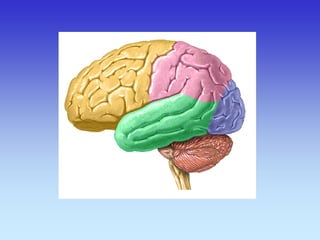

Frontal Lobe Lateral Sulcus

Parietal Lobe

Temporal Lobe